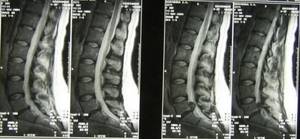

МРТ фото при секвестрированной грыже L5-S1

На первом МРТ фото прослеживается крупная грыжа после хирургического лечения. На фоне патологии у человека формируется сильный стеноз спинного мозга. Выпадение межпозвонкового диска располагается в сегменте L5-S1. Патология осложняется небольшим секвестром.

На основании магнитно-резонансных томограмм удается установить подвижность небольшого фрагмента. После чтения результата размеры выпячивания – в дорсальном направлении (14,5 мм), краниально-каудальном (26,8 мм).

На МРТ поясничного отдела позвоночника №140 визуализируется состояние после оперативного лечения рецидивирующей грыжи и стеноза спинномозгового канала.

Состояние человека было тяжелым на протяжении нескольких месяцев. При использовании анальгетических средств нельзя было купировать нозологию. Человек длительно отказывался от хирургического лечения, что привело к комплексу необратимых изменений поясничной области.

Только после того, как лекарственные препараты не приносили облегчения, человек вынужден был обратиться к врачу. Специалист при данных изменениях не может назначить эффективные консервативные препараты. Только операция по восстановлению структуры межпозвонкового диска избавляет от болевого синдрома.